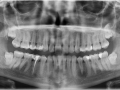

Rozległa torbiel zawiązkowa żuchwy

Paulina Adamska, Maria Mikołajska, Anna Janowska, Anna Starzyńska